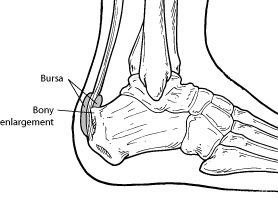

Haglund’s deformity is a bony enlargement on the back of the heel. The soft tissue near the Achilles tendon becomes irritated when the bony enlargement rubs against shoes. This often leads to painful bursitis, which is an inflammation of the bursa (a fluid-filled sac between the tendon and bone).

Haglund’s deformity is a bony enlargement on the back of the heel. The soft tissue near the Achilles tendon becomes irritated when the bony enlargement rubs against shoes. This often leads to painful bursitis, which is an inflammation of the bursa (a fluid-filled sac between the tendon and bone).